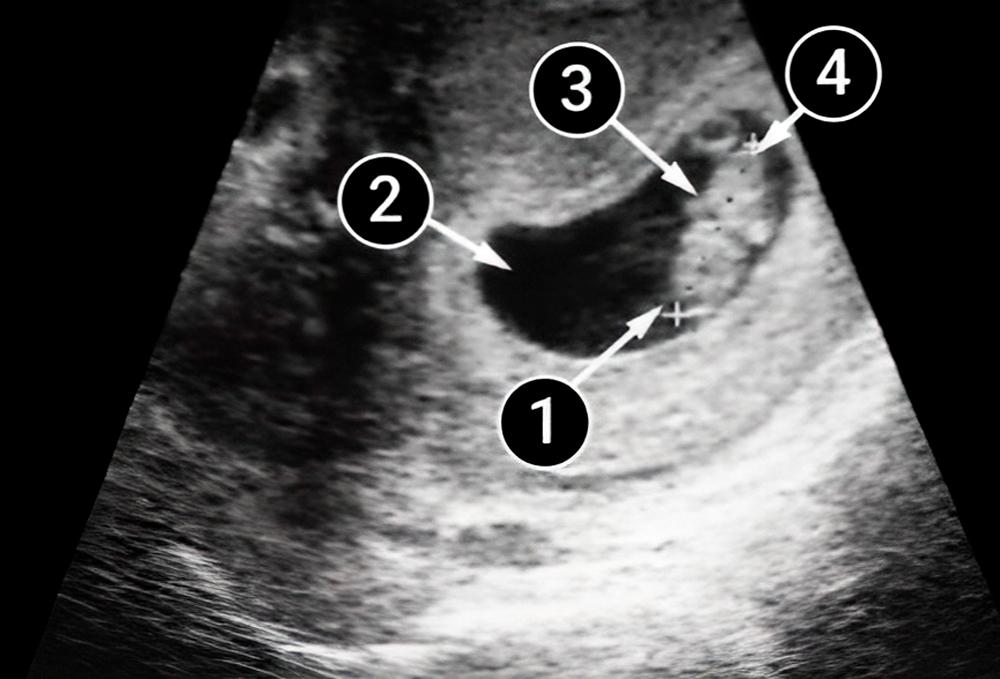

Lo que podemos ver en un ultrasonido

En la foto se puede ver un embrión diminuto en un saco amniótico de forma ovalada. Aunque el bebé ya se está moviendo, mamá aún no sentirá patadas ni aleteos. La cabeza, los brazos y las piernas del bebé están etiquetados.

Notarás que la cabeza es más grande que el cuerpo. El cuello y cuerpo del bebé empiezan a enderezarse. La línea de puntos negra en la imagen lo indica.

Los brazos en formación son visibles. En el lado izquierdo del cuerpo, cerca de donde los brazos se cruzan sobre el pecho del bebé, se puede ver un pequeño punto oscuro, que es el corazón.

Se ve un saco vitelino al lado de la pierna, que aparece como un anillo más claro con un centro oscuro. En esta etapa temprana del desarrollo, la nutrición y la actividad del bebé dependen del saco vitelino. La presencia del saco vitelino indica que el embarazo se desarrolla de forma correcta.